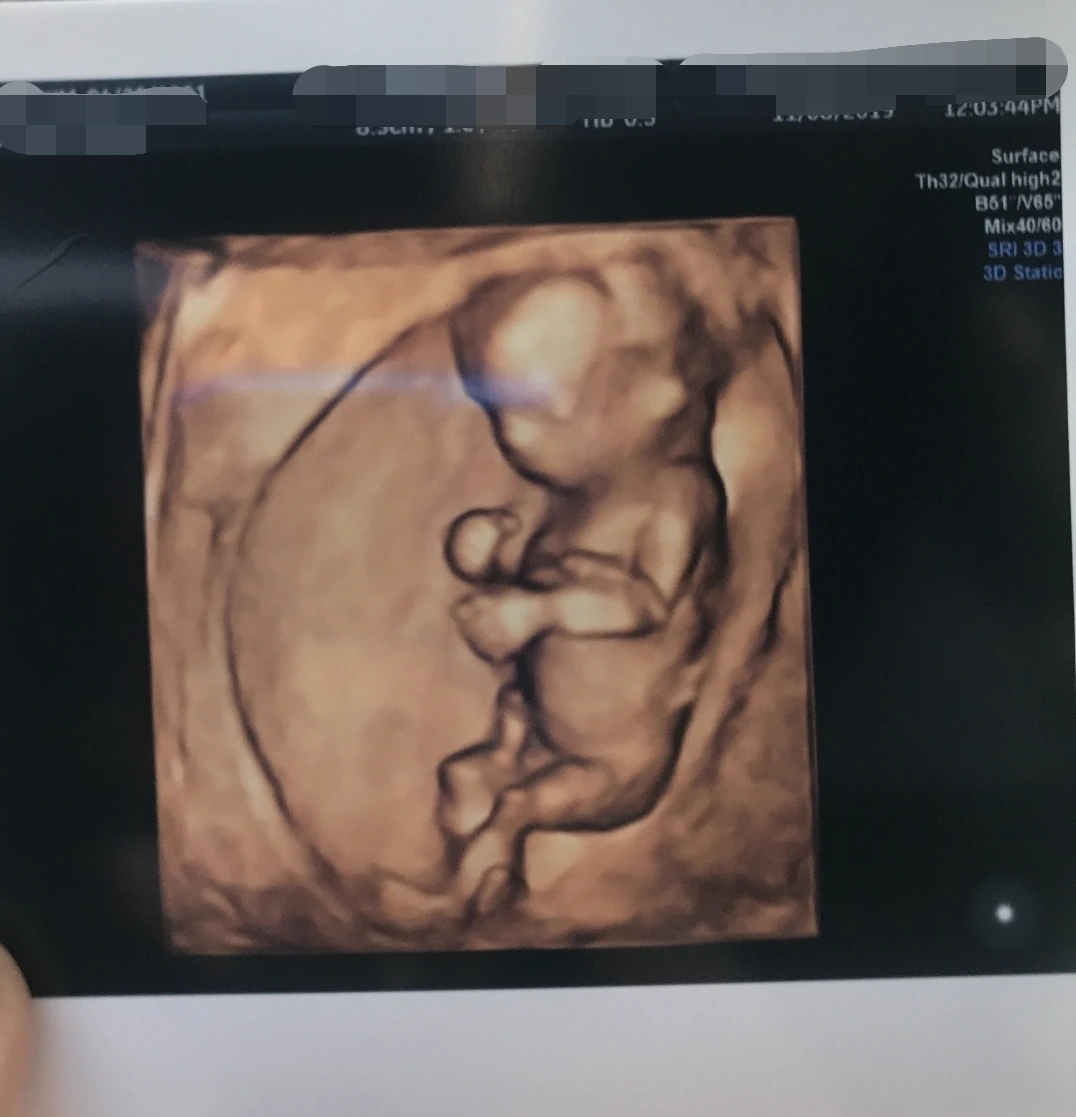

내 안의 자리잡은 너의 방, 고마워 나에게 와줘서

작고 소중해